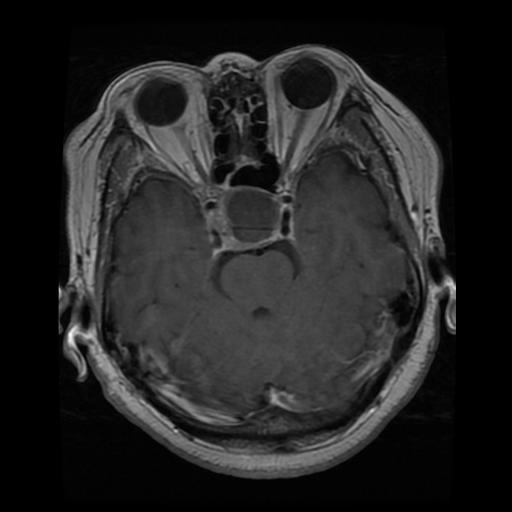

Figure 2: Samples of Meningioma segmentation across different imaging planes

Meningioma: Meningiomas arise from the meninges and are generally well‑circumscribed and homogeneous, making them easier to segment. However, their location adjacent to critical structures such as dural sinuses and cranial nerves can complicate diagnostic tasks. An example of a meningioma and its segmentation mask is presented in Figure 2, illustrating the clarity of its boundaries.